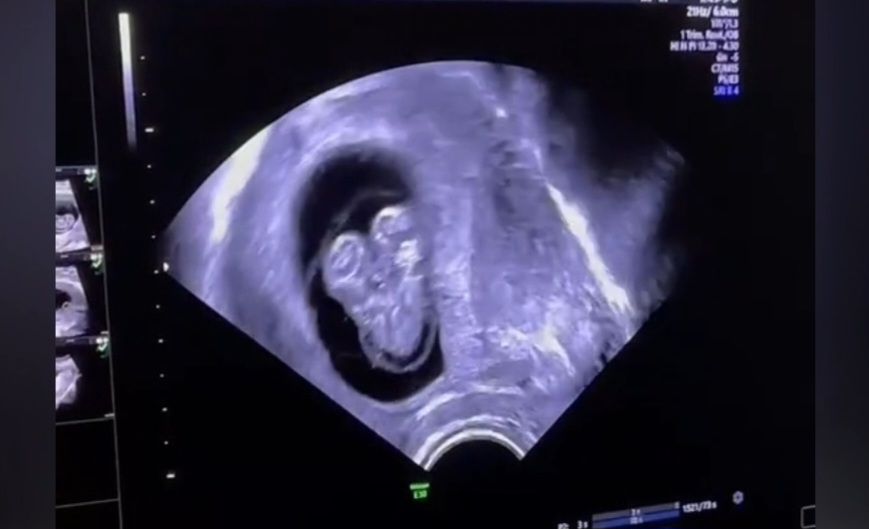

Azərbaycanda hamilədə Siam əkizləri görüldü - Video

Siam əkizləri hamiləlikdə nadir görülən döl patologiyasıdır. Azərbaycanda bu vaxta qədər Siam əkizləri doğulmayıb.

“Medicina” xəbər verir ki, Azərbaycanda inkişafdan qalmış hamiləlikdə dölün ikibaşlı, bir bədənə bitişik olduğu USM müayinəsində görülüb.

Siam əkizləri qüsurlu hamiləlikdir, inkişafdan qalması təbii prosesdir.

Qadın isə artıq üçüncü inkişafdan qalma hamiləliyi olduğunu bildirib.